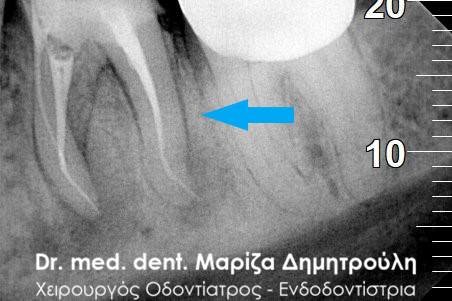

Η ακτινογραφική εξέταση αποκάλυψε ότι και τα δύο δόντια είχαν απονευρωθεί στο παρελθόν, έφεραν το καθένα στο εσωτερικό χυτό μεταλλικό άξονα και στο ακρορρίζιο διαπιστώθηκε μια περιακρορριζική αλλοίωση. Η αλλοίωση αυτή μαρτυρά τη φλεγμονή του δοντιού στο άκρο της ρίζας.

Αφού ολοκληρώθηκαν οι παραπάνω εργασίες πραγματοποιήθηκε αποκατάσταση των δοντιών με άξονες υαλονημάτων και κατασκεύη καινούριων στεφανών. Οπώς φαίνεται και στην τελική ακτινογραφία 6 μήνες μετά την διεκπεραίωση του σχεδίου θεραπείας η φλεγμονή στο ακρορρίζιο του δοντιού είχε ήδη υποχωρήσει.

ΠΡΙΝ

Έλεγχος αφαίρεσης άξονα και παλιάς απονεύρωσης

Τελική ακτινογραφία